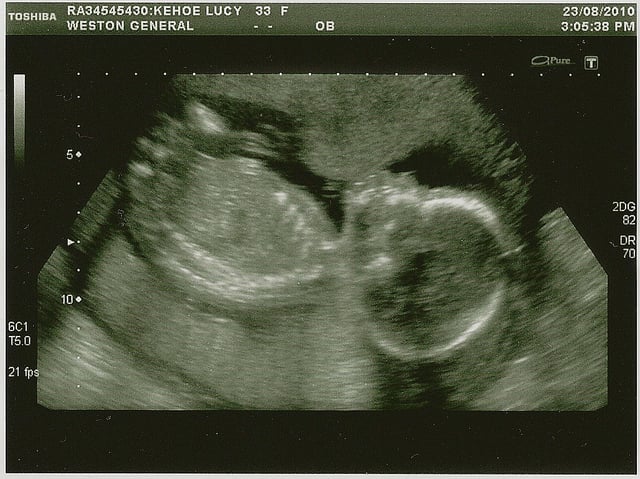

O Ultrassom Morfológico do 2º Trimestre é um exame crucial, geralmente realizado entre a 21ª e 24ª semana. Ele permite uma avaliação detalhada da anatomia fetal, identificando possíveis malformações e verificando o desenvolvimento dos órgãos. Converse com seu médico sobre a importância deste exame.

Ultrassom morfológico do segundo trimestre exibindo a imagem detalhada do rosto de um feto com 5 meses de gestação, em tons de cinza, com legendas técnicas impressas na borda inferior da tela.

O que é o ultrassom morfológico do segundo trimestre?

É um exame crucial para avaliar o desenvolvimento detalhado do bebê, verificando a formação de todos os órgãos e a presença de possíveis alterações. Geralmente é feito entre a 21ª e 24ª semana de gestação. É uma ótima oportunidade para ver seu filho com mais detalhes.